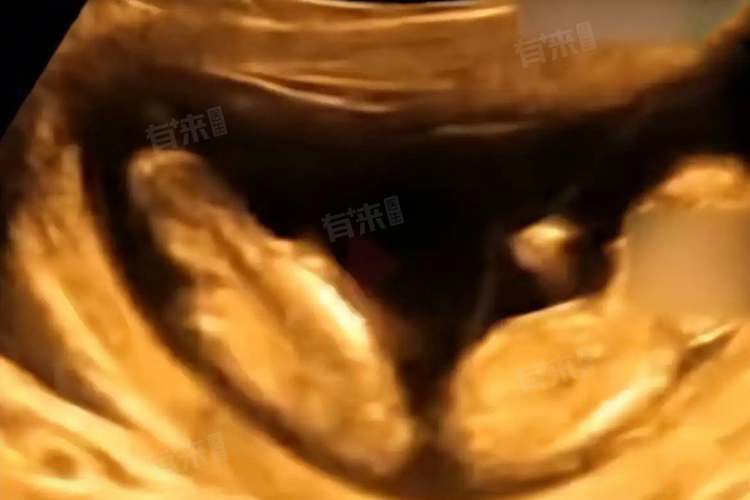

- 双胞胎分为同卵双胞胎和异卵双胞胎。同卵双胞胎是由一个受精卵在发育早期分裂成两个独立的胚胎,这两个胚胎具有相同的染色体和基因,所以性别必然相同,外貌也极为相似。而异卵双胞胎则是母亲在同一排卵周期内排出两个卵子,并且这两个卵子分别与不同的精子结合,形成两个独立的受精卵,各自发育成胚胎。这两个受精卵有着不同的遗传物质,性别可能相同,也可能不同,当性别不同时,就是所说的龙凤胎。

- 从遗传角度来讲,性染色体决定了胎儿的性别。女性的性染色体为XX,男性为XY。同卵双胞胎源自同一个受精卵,继承的性染色体一致,不可能出现性别差异。而异卵双胞胎因为来自不同的受精卵,有可能一个受精卵携带的性染色体是XX,发育成女胎;另一个受精卵携带的性染色体是XY,发育成男胎,从而形成龙凤胎。